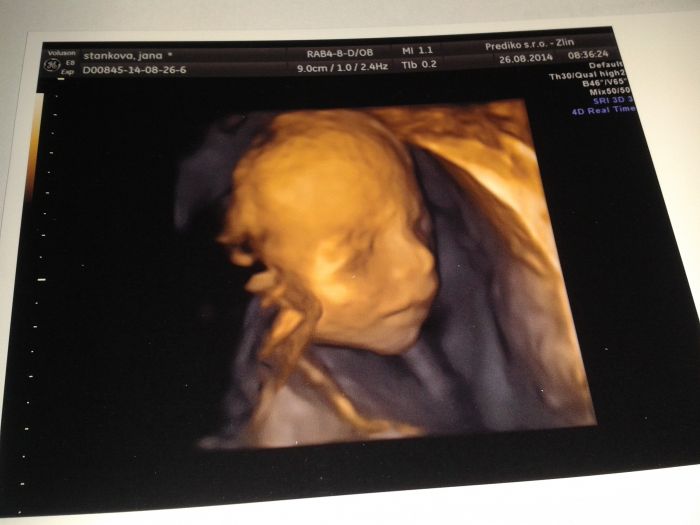

Ahojky holky dlooouho sem tu nebyla ale konverzace jede pod plnym proudem :-) uz mame po velkem ultrazvuku termin mame 9.1 a jestli cekame holcicku ci chlapecka to nevime pac pani doktorka rika kluk a pan doktor se prorekl a rikal mate ji krasnou :-D ale fotecku co udelal tak se povedla přeji vam krasny podvecer a slibuji ze budu psat casteji

Janco máš krásnou fotečku taky se těšim na 4D ultrazvuk a ve čtvrtek jdu na velkej tak už si nechám udělat fotečku tam jesli se něco nepodělá

[637722]Janči,to je krásná fotečka....jsem ráda,že jsi ty i mimčo v pohodě

Janči, krásná fotečka